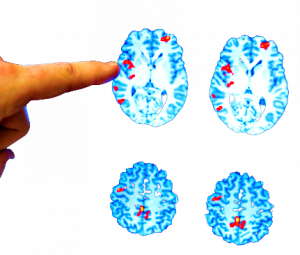

L'invecchiamento è il principale fattore di rischio per Alzheimer e malattia di Parkinson. Aggregati di proteine anomale si accumulano nel...

Un caso di demenza ogni tre secondi nel mondo e trend in continua crescita: se nel 2018 circa 50 milioni...